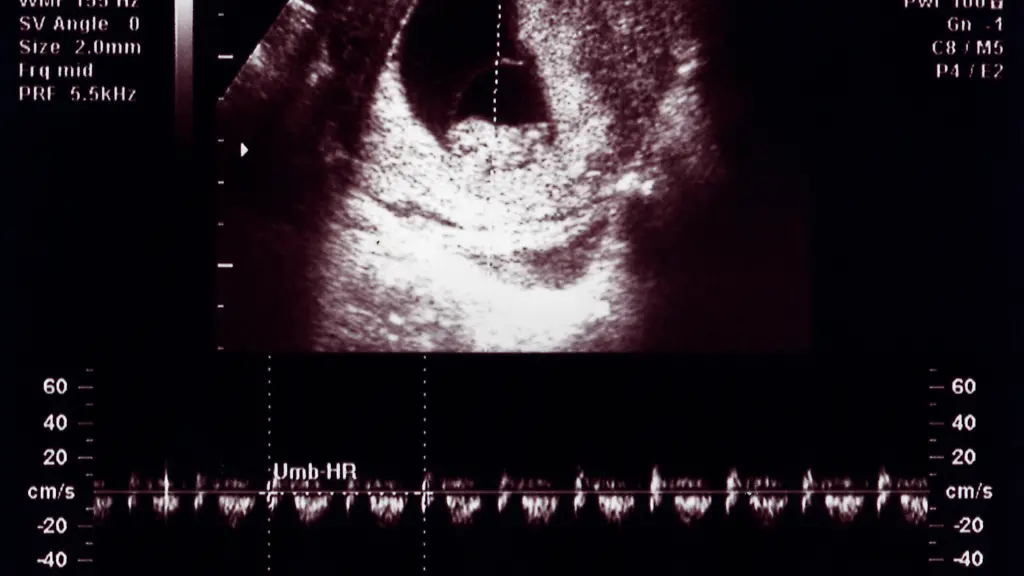

Wenige Wochen nach der umstrittenen Abtreibungsentscheidung des Obersten Gerichtshofes in den USA hat ein Bundesgericht entschieden, dass im Bundesstaat Georgia künftig strenge Regeln für Schwangerschaftsabbrüche gelten dürfen. Das Berufungsgericht des Bundes entschied, dass das sogenannte Herzschlag-Gesetz sofort in Kraft treten könne. Demnach dürfen Frauen in dem Bundesstaat ihre Schwangerschaft nicht mehr beenden, sobald der Herzschlag des Fötus festgestellt worden ist. Das kann bereits nach der sechsten Schwangerschaftswoche der Fall sein. Über das Gesetz aus Georgia war mehrere Jahre lang vor Gericht verhandelt worden.